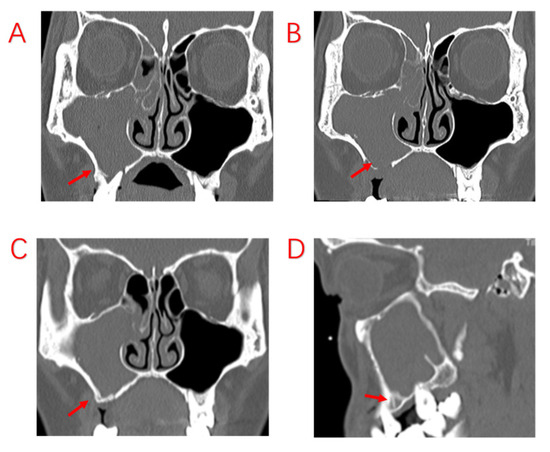

For patients with severe periodontal infection, it is difficult to improve the resorbed alveolar bone through treatment. Infection from the oral cavity will continue to irritate the maxillary sinus mucosa through the resorbed and destroyed alveolar bone. A total of 5 of the 103 patients had undergone ESS surgery, and although the sinus orifices were adequately opened, the inflammation of the sinus mucosa did not improve after surgery because the cause of the oral cavity was not addressed during the first treatment (Figure 5). During the second operation, we found no obvious purulent secretions in the maxillary sinus, but considerable mucosal swelling, which was associated with persistent irritation from the oral lesion, was found. Therefore, the oral lesion was removed during the surgery, and the symptoms completely disappeared. Hence, it is concluded that the best treatment plan for patients with EPL and PE with severe periodontal pathology, especially those with bone penetration in the MSF, should be sinus surgery combined with extraction of the affected teeth, removing the oral lesion, opening the maxillary sinus for drainage, and closing the oral maxillary sinus fistula as needed. In the authors’ opinion, there are two criteria for assessing the impact of odontogenic lesions in ODS surgical treatment. The first is whether the bone of the MSF has been penetrated. The second is whether the diseased tooth shows severe periodontal bone destruction and resorption. If both of these two criteria are met, ESS combined with the removal of the dental lesions is the best choice.

Figure 5.

Patient with severe periodontal infection and no improvement in sinusitis symptoms after ESS. (A,B): Sinus CT shows adequate maxillary sinus opening, alveolar bone resorption of the diseased tooth, and bone defects in the MSF. (C,D): MRI shows periodontal lesion tissue attached to the mucosa of the maxillary sinus, with significant swelling of the maxillary sinus mucosa. Red arrows indicate specific sites of bony defects in MSF.